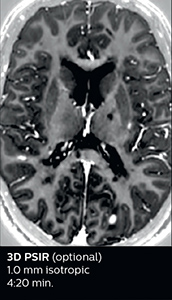

Dr. Savatovsky appreciates the improvements and flexibility that Elition with Compressed SENSE and MultiBand SENSE provides, particularly for stroke patients. “For stroke, it allows us to cut about 5 minutes off of our stroke protocol, or to keep the same acquisition time and get more insights.” The ability to perform more sequences can help in making a swift and confident diagnosis. “For example, our stroke cases usually include the regular sequences that every center does (b1000 diffusion, FLAIR, time-of-flight angiography), but we also image supra aortic vessels, and we can replace a gradient echo sequence with a fast 50-second susceptibility-weighted sequence, and all of this doesn’t add much time. because all the regular sequences are accelerated on Elition.” “The time savings with Compressed SENSE and MultiBand SENSE make it easier to add sequences to give us additional insights. Depending on the context and the first results, we might add a DSC perfusion to assess the ischemic penumbra, an ASL perfusion to help find an alternative cause in case of normal diffusion, or add a high-resolution T1 sequence for a stroke patient, to quickly assess wall imaging in emergency cases. The additional sequences can help improve patient management, because we can already consider some alternative diagnoses if the morphological MRI is normal.”

Using MultiBand SENSE allowed the staff to improve their diffusion quality. “Our diffusion sequence was already fast before, about 40 seconds. Now with Elition, it still lasts 40 seconds, but we improved the spatial resolution by 0.2 mm and use high b-values to be more sensitive to visualize changes related to acute stroke,” says Dr. Savatovsky. “We now also developed a high resolution DTI sequence (1.3 x 1.3 x 2 mm) that can be reformatted and takes 2 to 5 minutes depending on the coverage. We use it every time we have a doubt, or when we expect the diffusion to be abnormal but don’t see that on the fast sequence. We occasionally spot small ischemic infarctions that would not have been visible with the regular diffusion sequence.”

This is an example of acute ischemic stroke with distal occlusion of the right posterior cerebral artery. Note the improved visibility of the ischemic territory on the diffusion weighted image with high b-value. The 3D FLAIR shows a distal PCA occlusion. The fast SWIp depicts the thrombus on the isolated second echo image. The total scan time (including SmartBrain, preparations and a fast 3D T1w TSE Gd) is 8:00 minutes.